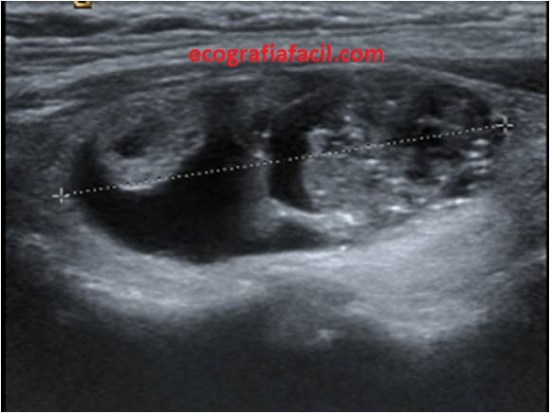

Esta semana subí una imagen a las stories de Instagram donde podíamos ver dos lesiones mamarias, dos nódulos, uno anecoico y otro hiperecogénico. Os pregunté qué veíais en la imagen, con dos opciones para contestar, la primera opción era que podían ser dos quistes, verdadera, y la segunda opción, un nódulo sólido y un quiste, la mayoría de las respuestas, por encima del 90%, escogisteis un nódulo sólido y otro quístico. Image 1.

Sabía que os iba a llevar al huerto esa foto, era difícil, en una sola foto podía ocasionar la duda más que razonable que el nódulo hiperecogénico fuera sólido, pero realmente, los dos nódulos eran quistes.

El anecoico no generaba dudas. El otro, todas. Y la pregunta que muchas me hicisteis era que cómo podía ser un quiste el nódulo hiperecogénico. Este post es aclaratorio y con las fotos lo vais a entender.

Ese nódulo de aspecto redondo, hiperecogénico de bordes definidos y buena transmisión es lo que en argot ecográfico de la mama llamamos quiste viejo. Te cuento… Los quistes sabemos que son estructuras más o menos ovaladas, bien definidas que transmiten muy bien, de borde bien definidos y lisos y anecoicas con refuerzo posterior.

Son quistes que cuando se extraen por PAAF lo que extraen las radiólogas suele ser una sustancia serosa, líquida, del color de un café muy aguado, son los típicos quistes mamarios…¿qué pasa? En ocasiones, con el paso del tiempo, estos quistes pueden modificar su aspecto interno y ecográfico, cambiando a una sustancia mucho más grasa y que cuando se evacúan tiene una aspecto mucho más denso, pastoso, muy graso, de color crema, siempre y cuando sea un quiste no complicado con pus o sangre u otras…esto es lo que conocemos «quistes viejos», y esto es justamente lo que le pasó a ese nódulo quístico de aspecto ecogénico, que era un quiste que había cambiado su aspecto.

Cambian su aspecto de este modo, normalmente son anecoicos siempre, luego empiezan a cambiar hasta que son mitad anecoicos, mitad ecogénicos, como la imagen 2 y luego son totalmente ecogénicos como el quiste ecogénico de la foto 1.

La radióloga puede tener dudas en algunas exploraciones, si por ejemplo es la primera exploración que se realiza la paciente apareciese este tipo de lesiones, entonces determinará ampliar con un estudio mediante intervencionismo o bien con control ecográfico, en este caso, no hizo falta pinchar el nódulo, vimos a ese quiste envejecer durante los controles que la paciente se realizaba regularmente y vimos cómo cambió de anecoico a hiperecogénico paulatina y lentamente año tras año, control tras control, primero siendo anecoico, luego parcialmente ecogénico y finalemente ecogénico por completo, siempre del mismo tamaño y colocado en la misma posición, por eso, en este caso no requirió análisis de Anatomía Patológica.